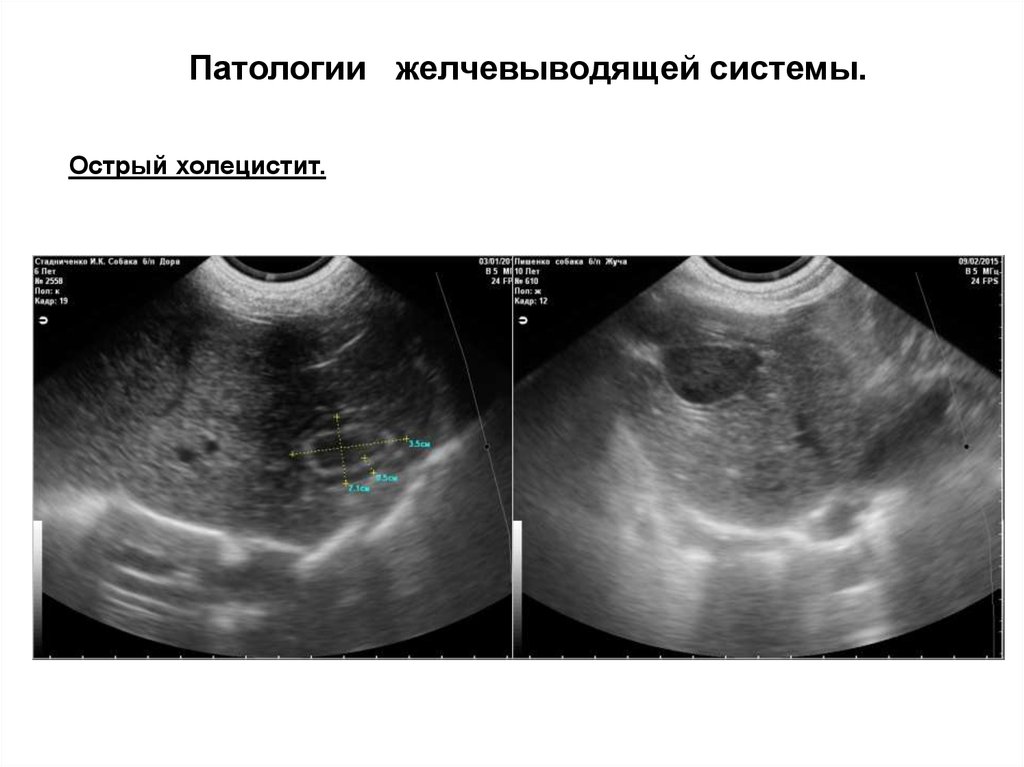

Патологии желчевыводящей системы.

1. Острый холецистит.

2. Хронический холецистит

Острый холецистит.